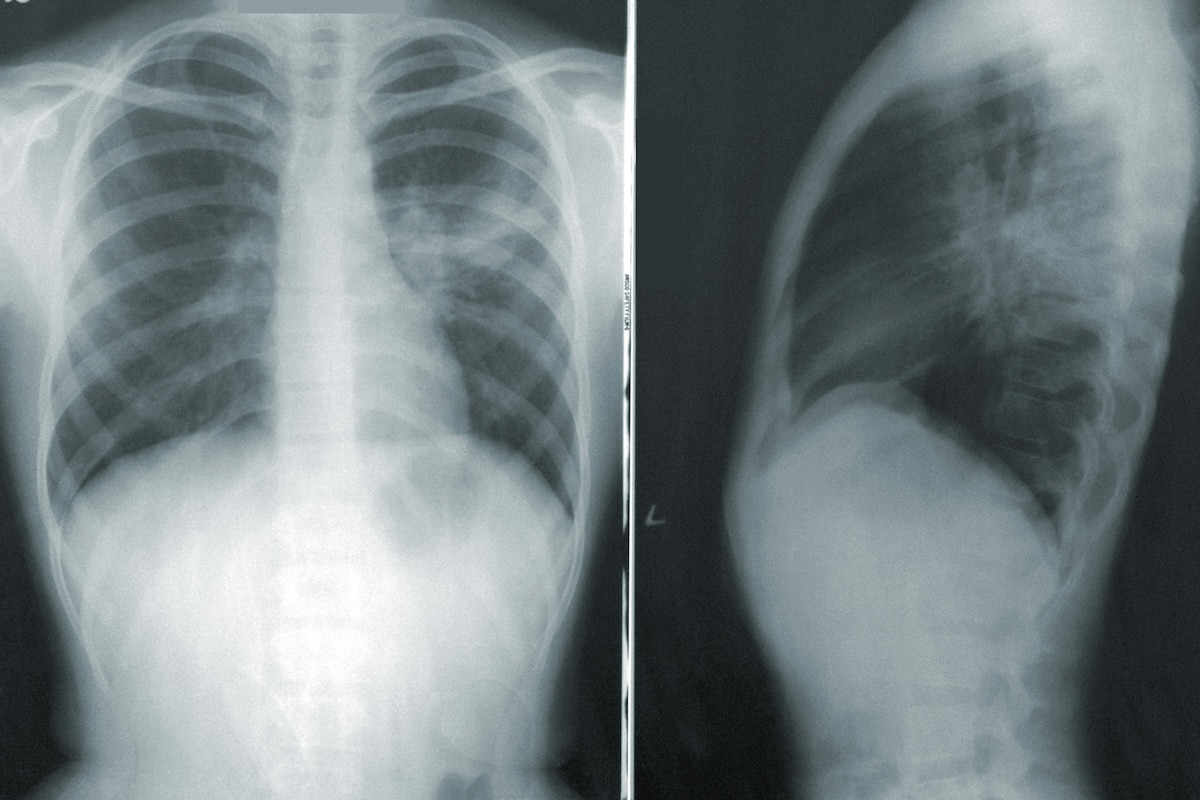

Με βάση τα ευρήματά τους, οι επιστήμονες προτρέπουν τους γιατρούς να παρακολουθούν στενά τους ασθενείς που έχουν αναρρώσει από σοβαρή COVID, γρίπη ή πνευμονία, ώστε να εντοπίζεται έγκαιρα ο καρκίνος του πνεύμονα, όταν είναι πιο εύκολα θεραπεύσιμος.

«Γνωρίζουμε εδώ και πολύ καιρό ότι παράγοντες όπως το κάπνισμα αυξάνουν τον κίνδυνο καρκίνου του πνεύμονα. Τα αποτελέσματα αυτής της μελέτης δείχνουν ότι ίσως χρειάζεται να αντιμετωπίζουμε με παρόμοιο τρόπο και τις σοβαρές ιογενείς λοιμώξεις του αναπνευστικού. Για παράδειγμα, σε ορισμένους ασθενείς με υψηλό κίνδυνο καρκίνου του πνεύμονα λόγω ιστορικού καπνίσματος, συνιστούμε στενή παρακολούθηση με τακτικές αξονικές τομογραφίες θώρακα ώστε να εντοπίζεται ο καρκίνος σε πρώιμο στάδιο. Σε μελλοντικές μελέτες ίσως χρειαστεί να εξετάσουμε μια αντίστοιχη προσέγγιση και μετά από σοβαρή ιογενή λοίμωξη του αναπνευστικού».